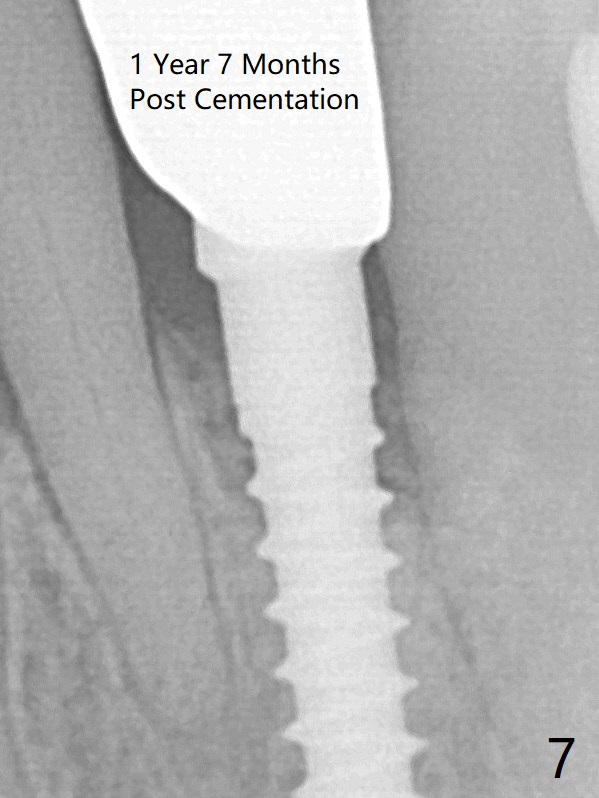

The gingival depth is measured 2-4 mm after extraction. The 1st intraop PA taken with 1.2 mm drill for 16 mm shows the mesiodistal width is 5.11 mm (Fig.2); a 2.5x14(2) mm 1-piece implant is placed with >35 Ncm (Fig.3 with allograft placed). There is no bone loss 3 months postop (Fig.5). The distal crest seems to be reduced in density and lower in height 1 year 7 months (Fig.7) and 1 year 11 months (Fig.8) post cementation. The severity does not worsen probably related to use of water pik.